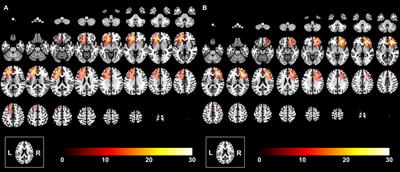

Decreased BOLD signals elicited by 40-Hz auditory stimulation of the right primary auditory cortex in bipolar disorder: An fMRI study